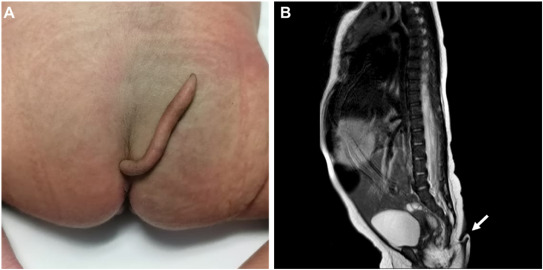

Se trata de una bebé que nació sin complicaciones y sana en Nuevo León. Excepto que la pequeña venía acompañada por una cola en la hendidura interglútea. La misma medía 5.7 centímetros de largo.

“Un apéndice caudal o cola humana es una protuberancia dorsal en la región lumbar, sacrococcígea o paraanal, que generalmente se diagnostica después del nacimiento. La estructura en forma de cola medía 5,7 cm de largo, con un diámetro entre 3 mm y 5 mm en toda su longitud, cilíndrica y puntiaguda hacia el final”, explicó en el artículo científico el Journal of Pediatric Surgery Case Reports

Fue entones hasta el momento del nacimiento que los doctores notaron la presencia de la cola. De tal modo, los especialistas comenzaron a realizar pruebas en la extremidad adicional para saber con lo que estaban tratando. Llegando así al siguiente paso: “La estructura era suave, cubierta de piel y cabello fino, podía moverse pasivamente sin dolor, pero no mostraba movimiento espontáneo. El bebé lloró cuando le pincharon la estructura con una aguja. La palpación de las estructuras óseas lumbosacras era normal y, por lo demás, el bebé parecía sano. También se notó la presencia de melanocitosis congénita en la región lumbosacra”, puntualizaron.

“Se realizó una radiografía Lumbosacra, sin evidencia de anomalías ni estructuras óseas en el interior de la cola. Además, el examen de audición y cardíaco fue normal, y el bebé fue dado de alta para seguimiento ambulatorio. La ecografía abdominal descartó malformaciones renales y del tracto urinario, o reflujo vesicoureteral. La resonancia magnética nuclear no mostró anomalías cerebrales y fue negativa para disrafismo posterior, con médula espinal y cono espinal de características normales”.